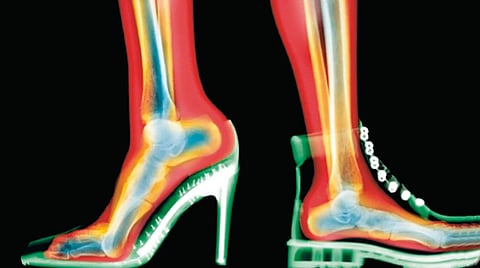

टोकदार पुढील भाग असलेली पादत्राणे फॅशनच्या जगात लोकप्रिय असली तरी ती बोटांना एकमेकांवर दाबतात. त्यामुळे गोखरू, नसांवर दाब येणे, नख आत वाढण्याची समस्या, वेदनादायक कडक गाठी निर्माण होतात आणि कालांतराने बोटांचा नैसर्गिक आकारही बदलू शकतो. दिसायला साध्या व आरामदायक वाटणार्या बॅले प्रकारच्या सपाट चप्पलांमध्ये कमानीचा आधार किंवा कुशनिंग जवळजवळ नसते. त्यामुळे प्रत्येक पावलागणिक पायांना अधिक मेहनत करावी लागते. परिणामी प्लांटर फॅसिआयटिस, टाचदुखी आणि घोट्यात ताण निर्माण होतो.

जड तळाच्या चंकी प्रकारच्या चप्पला किंवा प्लॅटफॉर्म पादत्राणे ट्रेंडी असली तरी त्या अनेकदा स्थिर नसतात. कठीण तळामुळे पाय नैसर्गिकरीत्या वाकत नाही, चालण्याची पद्धत बदलते, समतोल बिघडतो आणि घोटा वाकण्याची शक्यता वाढते. त्याचा ताण गुडघे आणि कुल्ह्यांवरही येतो. समाजमाध्यमांवरील प्रभावक संस्कृतीमुळे ‘स्टाईल’साठी अस्वस्थ करणारी पादत्राणे घालण्याकडे अनेकजण जाणूनबुजून दुर्लक्ष करतात. दीर्घकाळ उभे राहणे, कार्यक्रमांत औपचारिक दिसण्याची अपेक्षा आणि ‘सौंदर्यासाठी वेदना सहन कराव्याच लागतात’ ही मानसिकता पायांच्या तक्रारी अधिक तीव्र करत आहे. त्यामुळे पूर्वी वय वाढल्यानंतर दिसणार्या समस्या आता तरुणींमध्येही दिसू लागल्या आहेत.